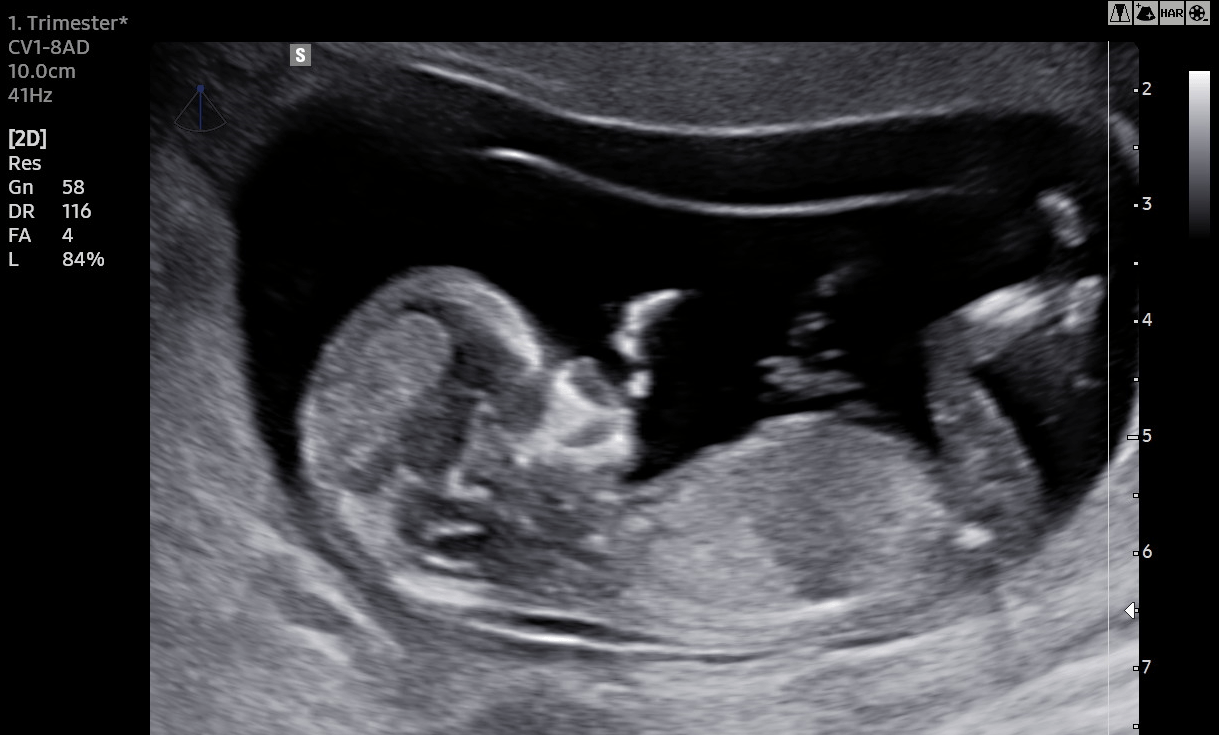

Frühe Feindiagnostik/NIPT

Die "frühe Feindiagnostik" ist eine komplexe Ultraschalluntersuchung des Feten und seiner umgebenden Strukturen zum Ausschluß von Hinweisen für eine genetische Anomalie oder eine körperliche Fehlbildung.

Sie wird in der 12.-14. Schwangerschaftswoche durchgeführt und bedarf neben einer guten Gerätetechnik eine hohe Expertise des Untersuchenden.

Ergänzend zu dieser Untersuchung besteht die Möglichkeit der Durchführung eines "Nicht invasiven Pränataltest" (NIPT) zum gezielten Ausschluß der Trisomien 21 (Down-Syndrom), 18 und 13, sowie zur Bestimmung des individuellen Präeklampsierisiko. Näheres dazu finden Sie hier.

Alle genannten Untersuchungen werden in unserer Praxis durchgeführt.

Sie können gerne eine Begleitperson ihrer Wahl mitbringen. Da diese Untersuchung ein hohes Maß an Konzentration erfordert, bitten wir von der Mitnahme von Kinder unter 12 Jahren abzusehen.

Zur Gewährleistung einer hohen Bildqualität bitten wir Sie, ihren unteren Bauchabschnitt einige Tage vor der Untersuchung nicht einzucremen oder-ölen und vorhandene Piercings am Nabel zu entfernen.